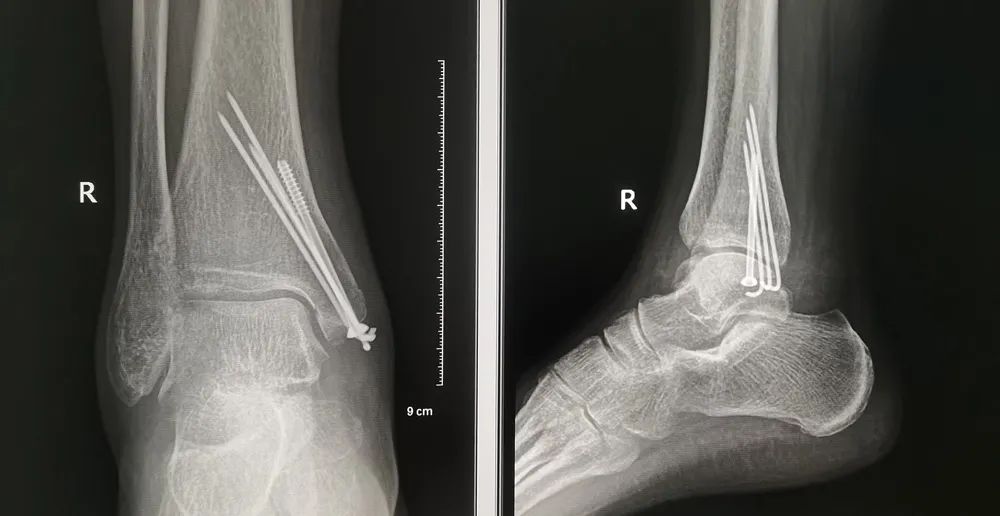

01、DR篇

這份影像檢查必備的“省心”秘籍,相信一定會幫助到您!

DR(直接數(shù)字化X射線攝影系統(tǒng),簡稱X線檢查)是一種比較常規(guī)的基礎影像學檢查方式,主要用于患者的胸部(肺炎、肺結核、胸腔積液、氣胸、外傷等)、腹部(胃腸道的梗阻、穿孔等)、脊柱以及四肢骨骼等檢查。